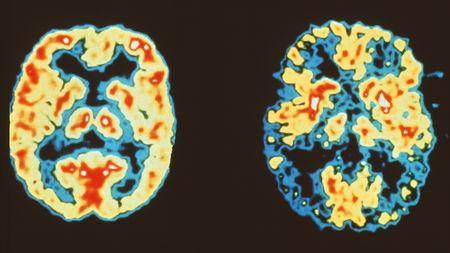

Brains without (left) and with (right) Alzheimer’s disease; Figure courtesy Science Magazine

The researchers analysed neurons from six healthy elderly people and seven patients reported to have Alzheimer’s disease. The patients had the most common form of Alzheimer’s - the non-inherited one. The researchers tested whether the brain cells got different forms of the gene for amyloid precursor protein (APP). Amyloid is the protein that forms plaques in the brain cells of people suffering from Alzheimer’s disease. The researchers considered APP as a good candidate because in a previous study they found that the gene for APP can have extra copies in the cells of Alzheimer’s patients. The increase arises from the process of somatic gene recombination.

What is more interesting, the Nature paper reports that the APP gene doesn’t make one or two extra copies, in fact, it produces thousands of different versions of the gene. In some of the versions, single nucleotide bases, the building blocks of the genetic code, are switched while in other versions they found that a portion of the DNA is removed and the remaining portions knitted together. They confirmed that neurons of Alzheimer’s patients contain six times more varieties of the APP protein than healthy people.